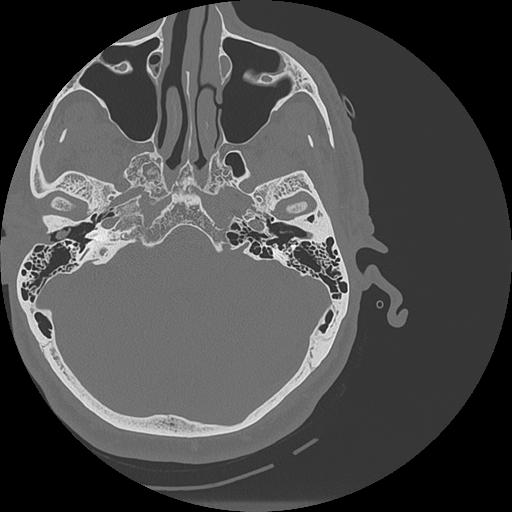

7 HUESO,,Vol,0.5,HUESO,,